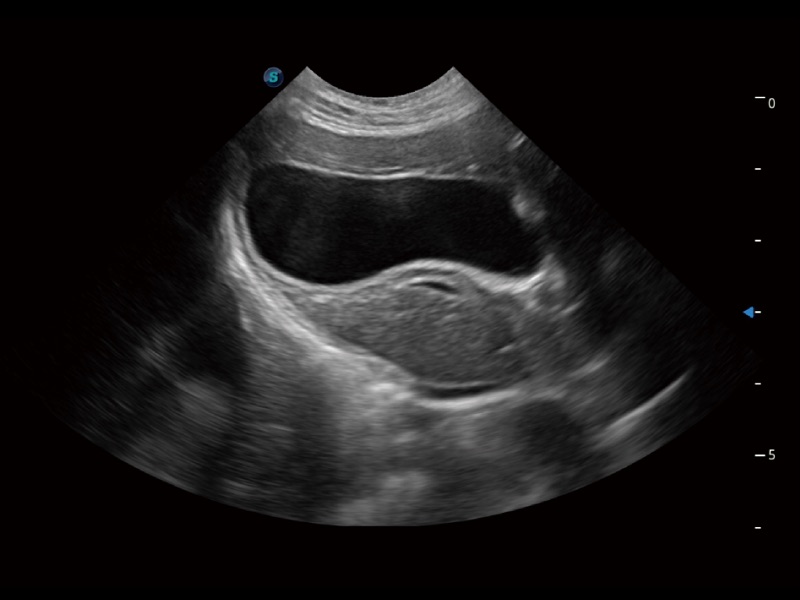

动物是人类最亲密的朋友和最值得信赖的伙伴。乐玩lewin国际也一直致力于探索动物专用的超声影像解决方案。全新推出的ProPet系列,是乐玩lewin国际在动物超声影像智能化、专业化、精准化的一次跨越式革新。动物不能用言语来表述自己的不适,通过超声影像,ProPet系列搭建了动物医生与不同物种沟通的“桥梁”,为动物医生注入了“治愈之力”。 ProPet 70将是您值得信赖的超声伙伴。它配备了复合材料线阵探头,帮助动物医生获得卓越精准的临床图像。同时ProPet 70直观便捷的操作体验以及专业的测量工具,可为不同体型和生理结构的动物带来全面临床评估,切实为动物医生提供智能、专业、精准的超声影像解决方案。

ProPet 70 进一步提升了微米成像算法,更加注重对基础原始图像的还原和保留,在有效减少斑点噪声、增强组织边界显示的同时,避免过度优化丟失真实的解剖信息。

ProPet 70专为动物医生设计,对不同的动物体型和生理结构作出了针对性的优化。通过动物影像专用软件,可满足个性化的应用需求,帮助动物医生获得更精确的诊断数据。